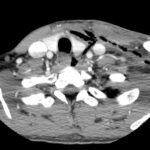

Necrotizing soft tissue infections with mediastinal extension are exceedingly rare. This submission provides dynamic and static visual stimuli (CT images) and a case report describing the history of present illness, initial ED presentation and inpatient course of a 33-year-old man who developed facial necrotizing fasciitis complicated by mediastinitis secondary to odontogenic infection following wisdom tooth extraction. Discussion of the key features of this rare presentation, the diagnostic and therapeutic approaches to making the diagnosis (including CT), and the role of the Emergency Physician, are highlighted.